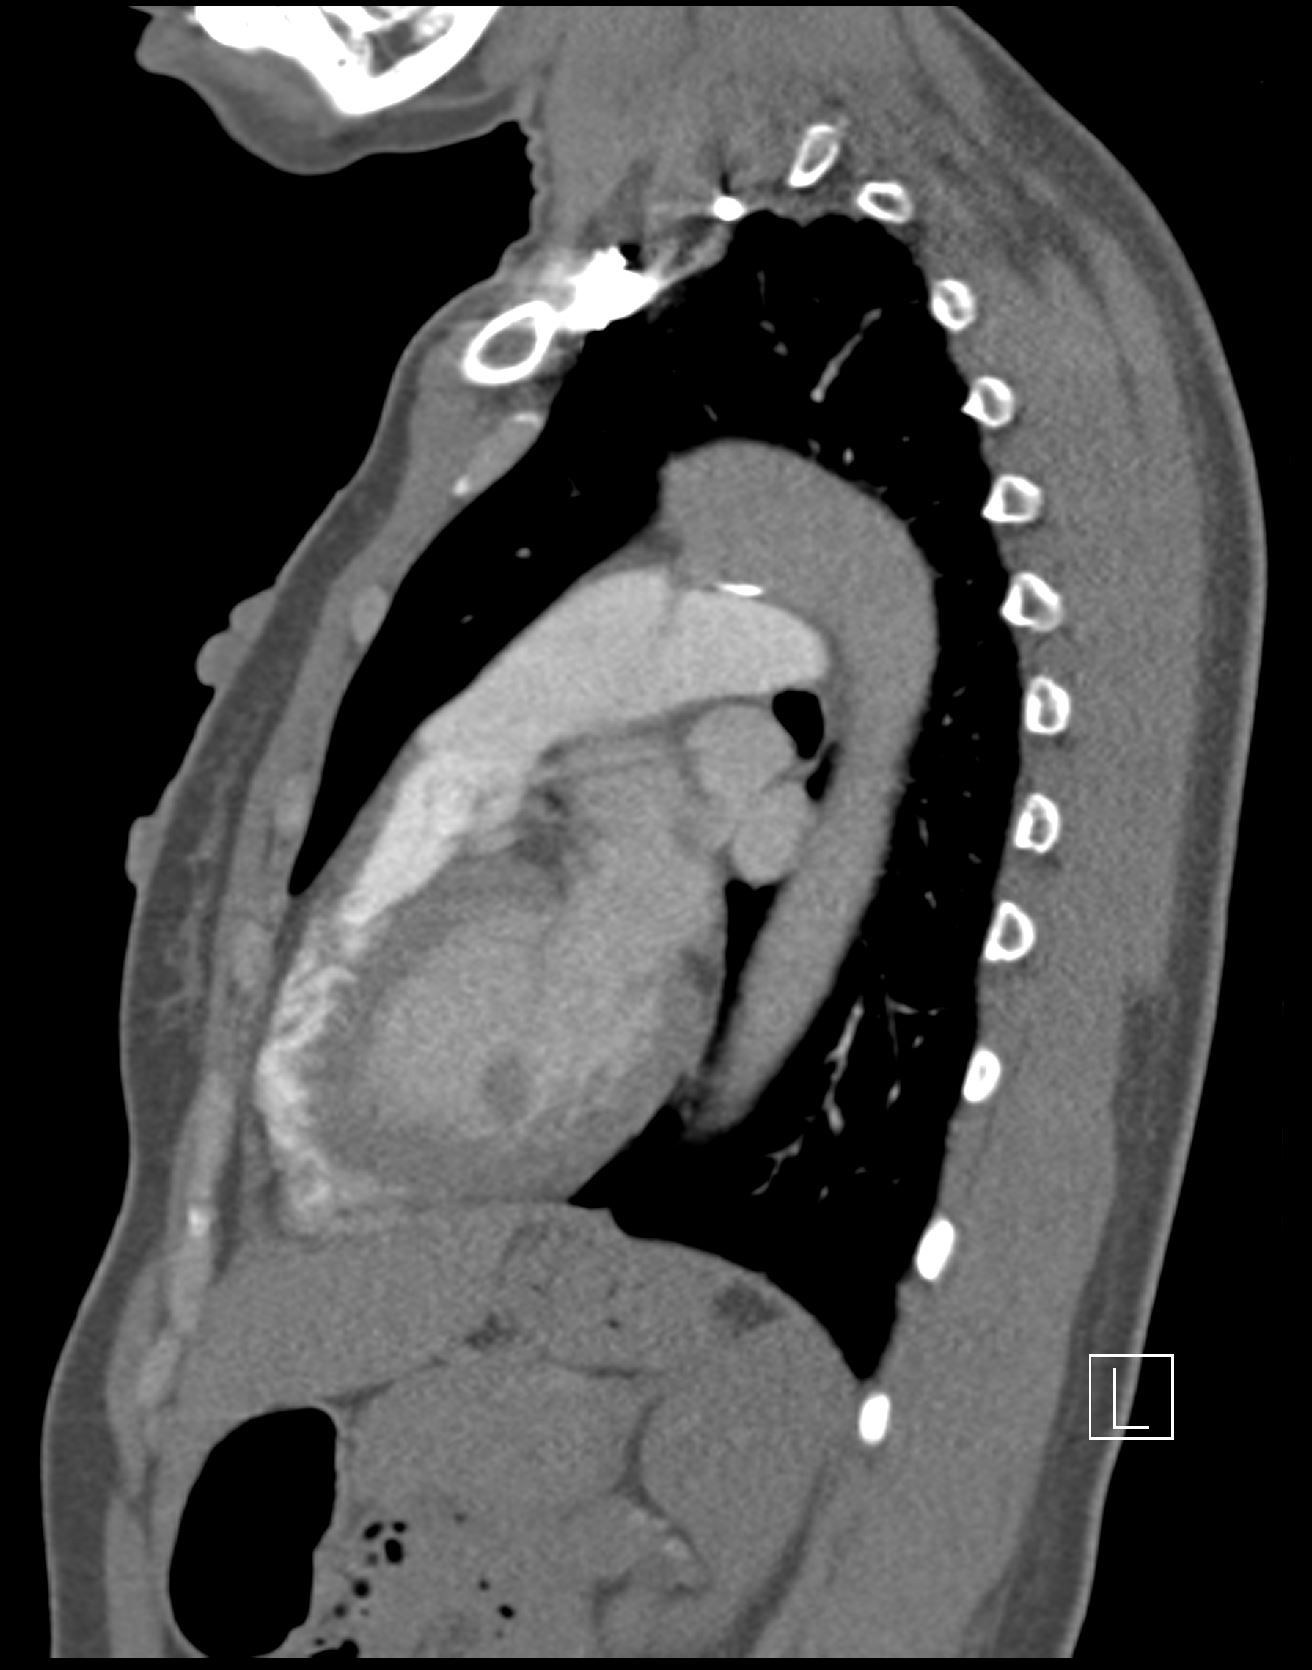

A 50-year old female presented with acute chest and epigastric pain. What is the diagnosis?